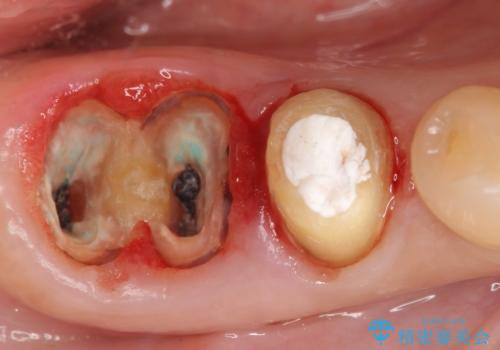

精査したところ、右下の奥歯(右下6)は割れており保存不可能な状態でした。

患者様のご希望により、右下大臼歯2本(右下76)のインプラント治療、右下小臼歯(右下5)の根管治療及び補綴治療を行いました。

割れていた歯の周囲組織の炎症が強く、骨の厚みが薄かったため、インプラント埋入時に骨増生(GBR)を行いました。